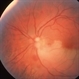

- embolus

- Calcified embolus in a patient with cardiac valve disease.